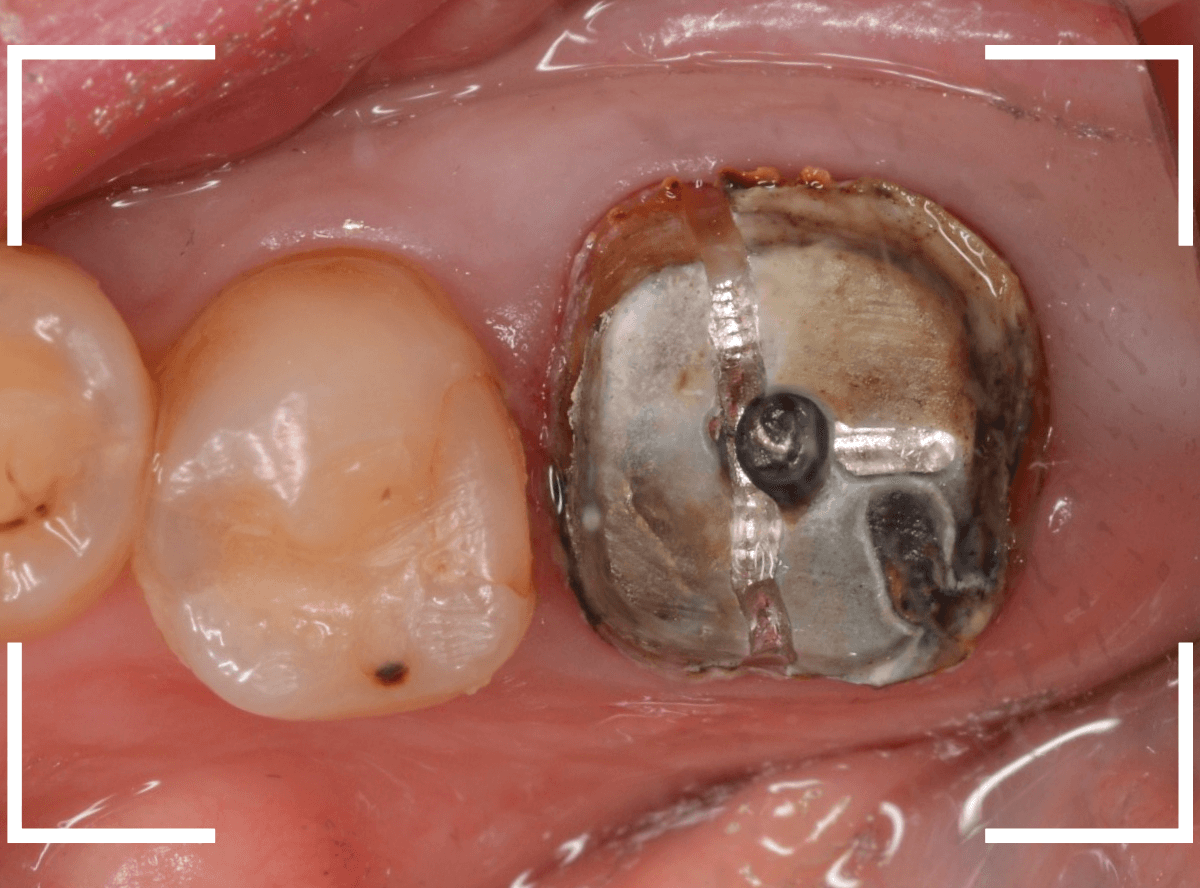

まずは、奥のメタル・クラウンを外します。

メタル・コアが入っていますが、こちらも慎重に外して、中を調べていきます。

レントゲン写真では問題なさそうでしたが、メタルコアを除去すると、中は真っ黒でした。

このように、コアの中で虫歯が進行している場合もありますので、さし歯をやり直す際は、出来る限りコアも外して調べるようにしています。